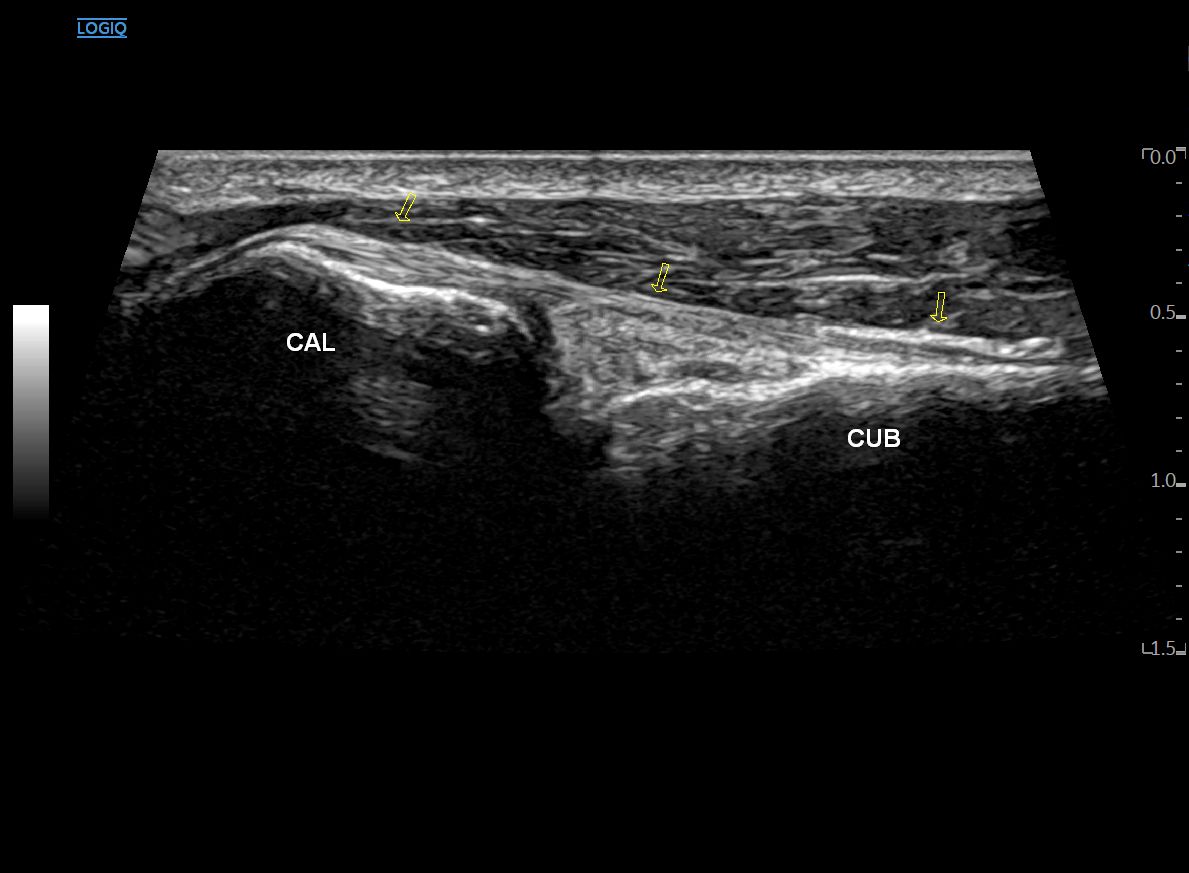

종골(CAL)과 입방골(CUB)이 만나는

종입방 관절이 보이고요.

그 위로 제5중족골을 향해 달려가는

단비골근건(PB)이 보입니다.

이분인대를 향해 프로브를 내측으로 이동하면

두 뼈를 연결하는 등쪽 종입방인대(Dorsal CCL)가 보이고요.

그 위로 짧은 발가락 폄근이

(단지신근, EDB, Extensor Digitorum Brevis)

보이기 시작합니다.